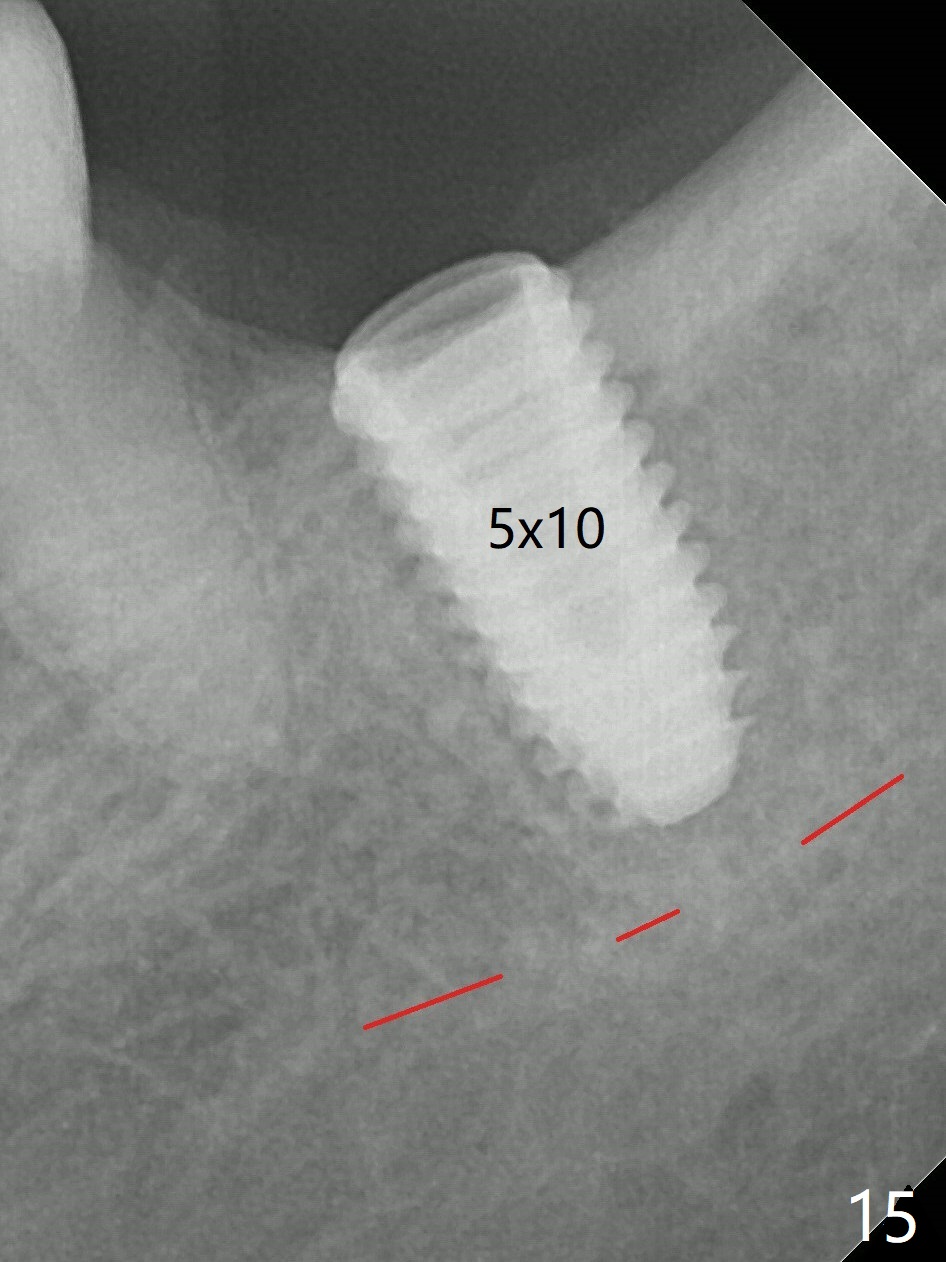

Preop palpation of the edentulous area at #18 does not show the flatness of the ridge top as shown by CBCT.  Incision reveals that the ridge is not as wide as CBCT indicates (Fig.1 (coronal section) between arrowheads).  In fact the ridge is concave (Fig.2 red dashed line).  Osteotomy is initiated in the middle of the concavity (Fig.2 green line) with insertion of 7 mm guide pin (Fig.3).   After removal of the pin, the osteotomy is moved buccally (Fig.4).  After Marking Bur and 4.3 mm Magic Drill, a 5x9 mm IBS implant is placed with 2.8 mm clearance from the Inferior Alveolar Canal (Fig.6).  Following deepening the osteotomy with Final Drill, the implant is placed deeper (Fig.7).  The osteotomy happens to be established in the mesial socket, since the distal socket has not completely healed (Fig.6 yellow dashed line).  Granulation tissue is removed.  Since the lingual crest is lower than the buccal one (Fig.1 B), there is lingual thread exposure after implant placement (Fig.5).  The exposed thread is covered by bone graft (autogenous bone, allograft and Osteogen, Fig.5 pink circles).  Some of the graft is apparently pushed into the distal socket (Fig.7 yellow dashed line) post GBR and suture.  As the implant is placed twice, insertion torque is <10 Ncm (although the implant is stable).  A 5x3 mm healing abutment is placed (Fig.7 H).

There is no apparent bone loss 4 months postop (Fig.10).  There is chewing pain in spite of occlusal adjustment 7 months post cementation (Fig.11-13: increased radiolucency around the implant).  The crown/abutment is removed and a healing abutment is placed (6x3 mm); the implant is stable.  The patient return for re-evaluation in 3 months (15 months postop); radiolucency appears to reduce (Fig.14).  But there is pain when the healing abutment is being removed.  After local anesthesia, the implant is removed with a wrench.  Following debridement of the osteototomy (intact, although tender), a 5x10 mm dummy implant with SLA surface is placed (Fig.15).  After 5.5 mm tap, a 5.5x8.5 mm implant is placed with >50 Ncm (Fig.16).  A 6.8x5 mm healing abutment is placed, followed by periodontal dressing.  Re-analysis of preop CBCT shows that the bone density at the site is low: 70 units average.  Progressive loading is necessary for this case 4-6 months postop.  The soft and hard tissues around the implant seem to heal 4 months postop (Fig.17).